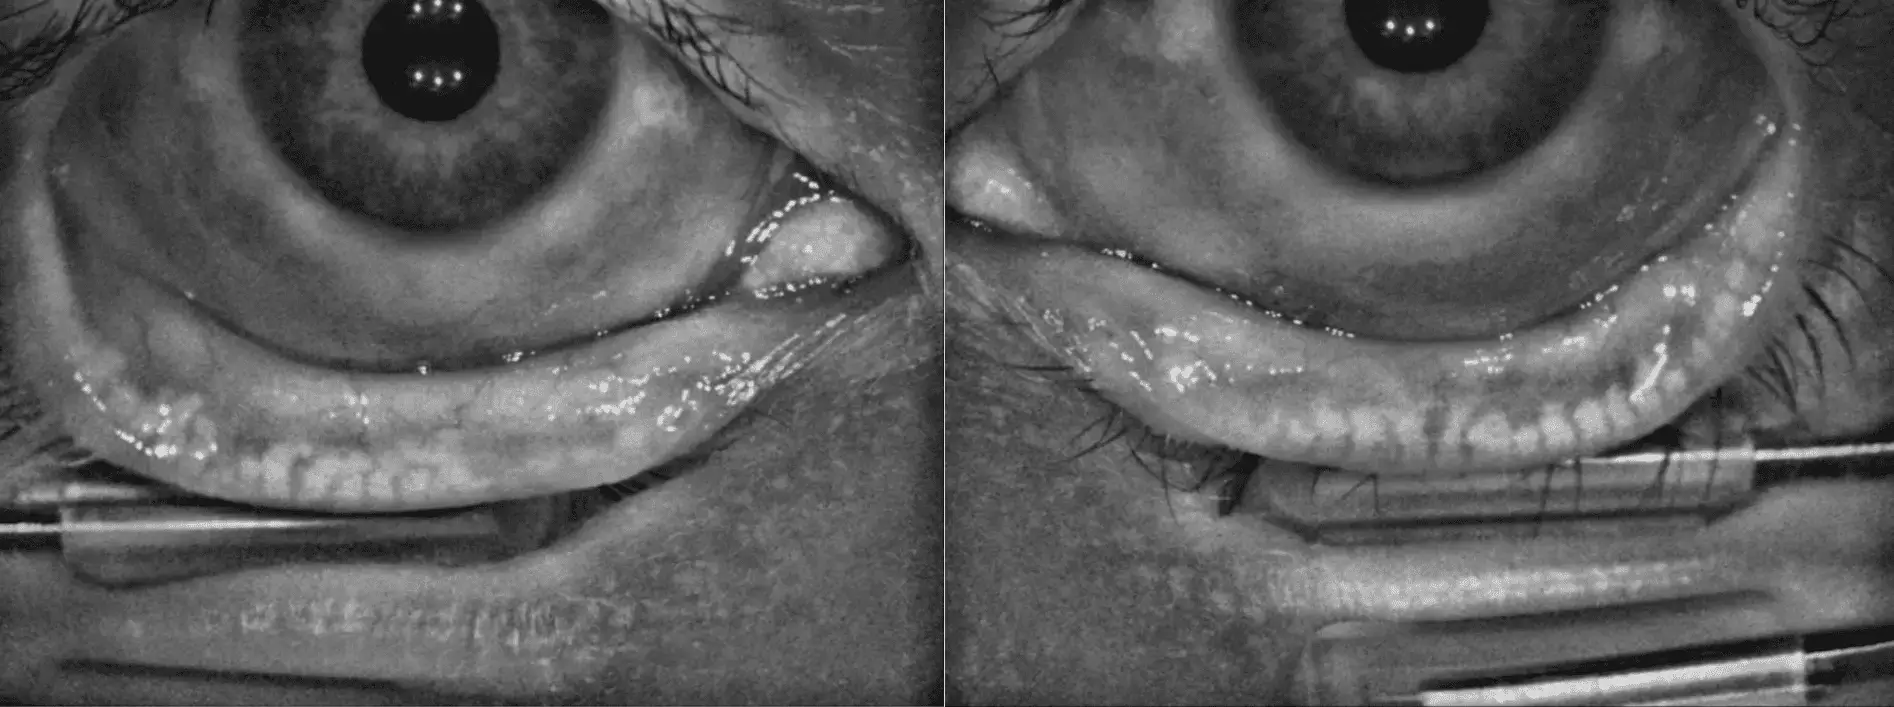

MGX à l'évaluation initiale après le IPL 1

MGX après le dernier traitement du protocole

Le meibum, initialement pâteux, est devenu plus fluide pour la plupart des glandes, confirmant l'amélioration de la fonction des glandes de Meibomius. L'osmolarité oculaire s'est également stabilisée, traduisant une meilleure qualité du film lacrymal.